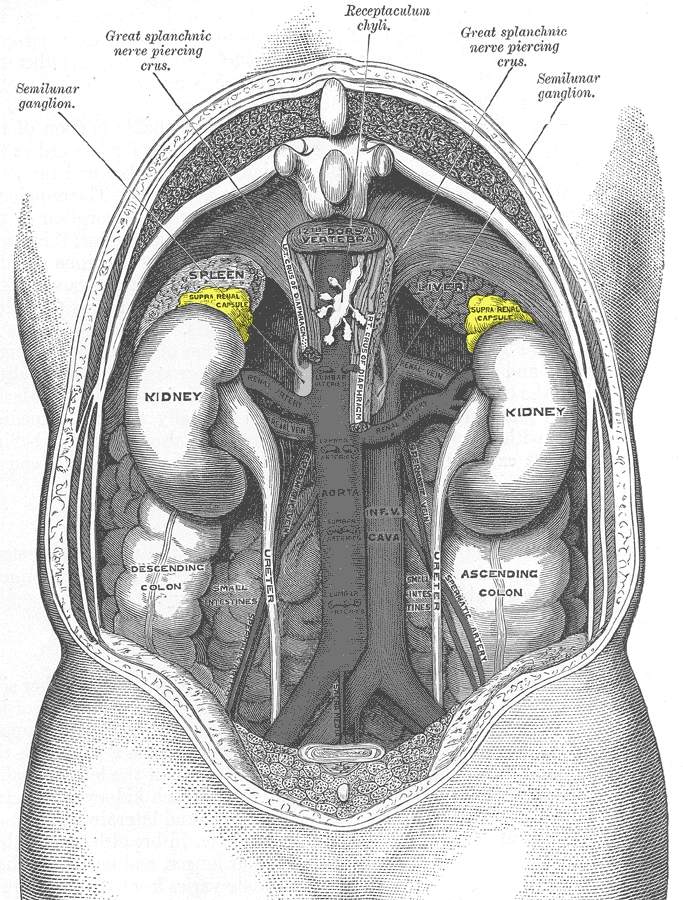

크롬친화세포종은 부신 수질에서 발생하는 드문 종양으로, 과도한 카테콜아민 분비를 특징으로 한다. 1800년대에 처음 보고되었으며, 고혈압, 두통, 발한, 심계항진 등의 증상을 유발한다. 유전적 요인이 약 40%를 차지하며, MEN2, VHL, NF1 등의 유전자 변이와 관련이 있다. 진단은 혈액 및 소변 검사, 영상 검사를 통해 이루어지며, 수술적 절제가 주요 치료법이다. 조기 진단과 치료가 중요하며, 치료가 늦어질 경우 심각한 합병증을 유발할 수 있다. 미디어에서도 이 질환이 다루어진 바 있으며, 희귀 질환 커뮤니티에서 "얼룩말"이라는 상징으로 표현되기도 한다.

영상 검사로는 CT, MRI, 131I-MIBG 신티그래피, PET 등이 있다.[82] CT와 MRI는 종양의 위치, 크기, 주변 구조와의 관계를 파악하는 데 유용하다.[82] 131I-MIBG 신티그래피는 부신 외 원발 병변이나 전이 병변의 위치를 확인하는 데 사용된다.[88] MIBG는 노르에피네프린과 유사한 구조를 가져 종양 세포에 섭취되는 원리를 이용한다. PET 검사는 MIBG 섭취가 없는 경우에도 양성으로 나타날 수 있으며, 전이 병변 검색에 유용하다.[90] 특히, 68Ga-DOTA 유사체를 이용한 PET 검사는 소마토스타틴 수용체 영상 기법으로, 다른 기능적 영상 검사보다 우수한 성능을 보인다.[94][95][97]